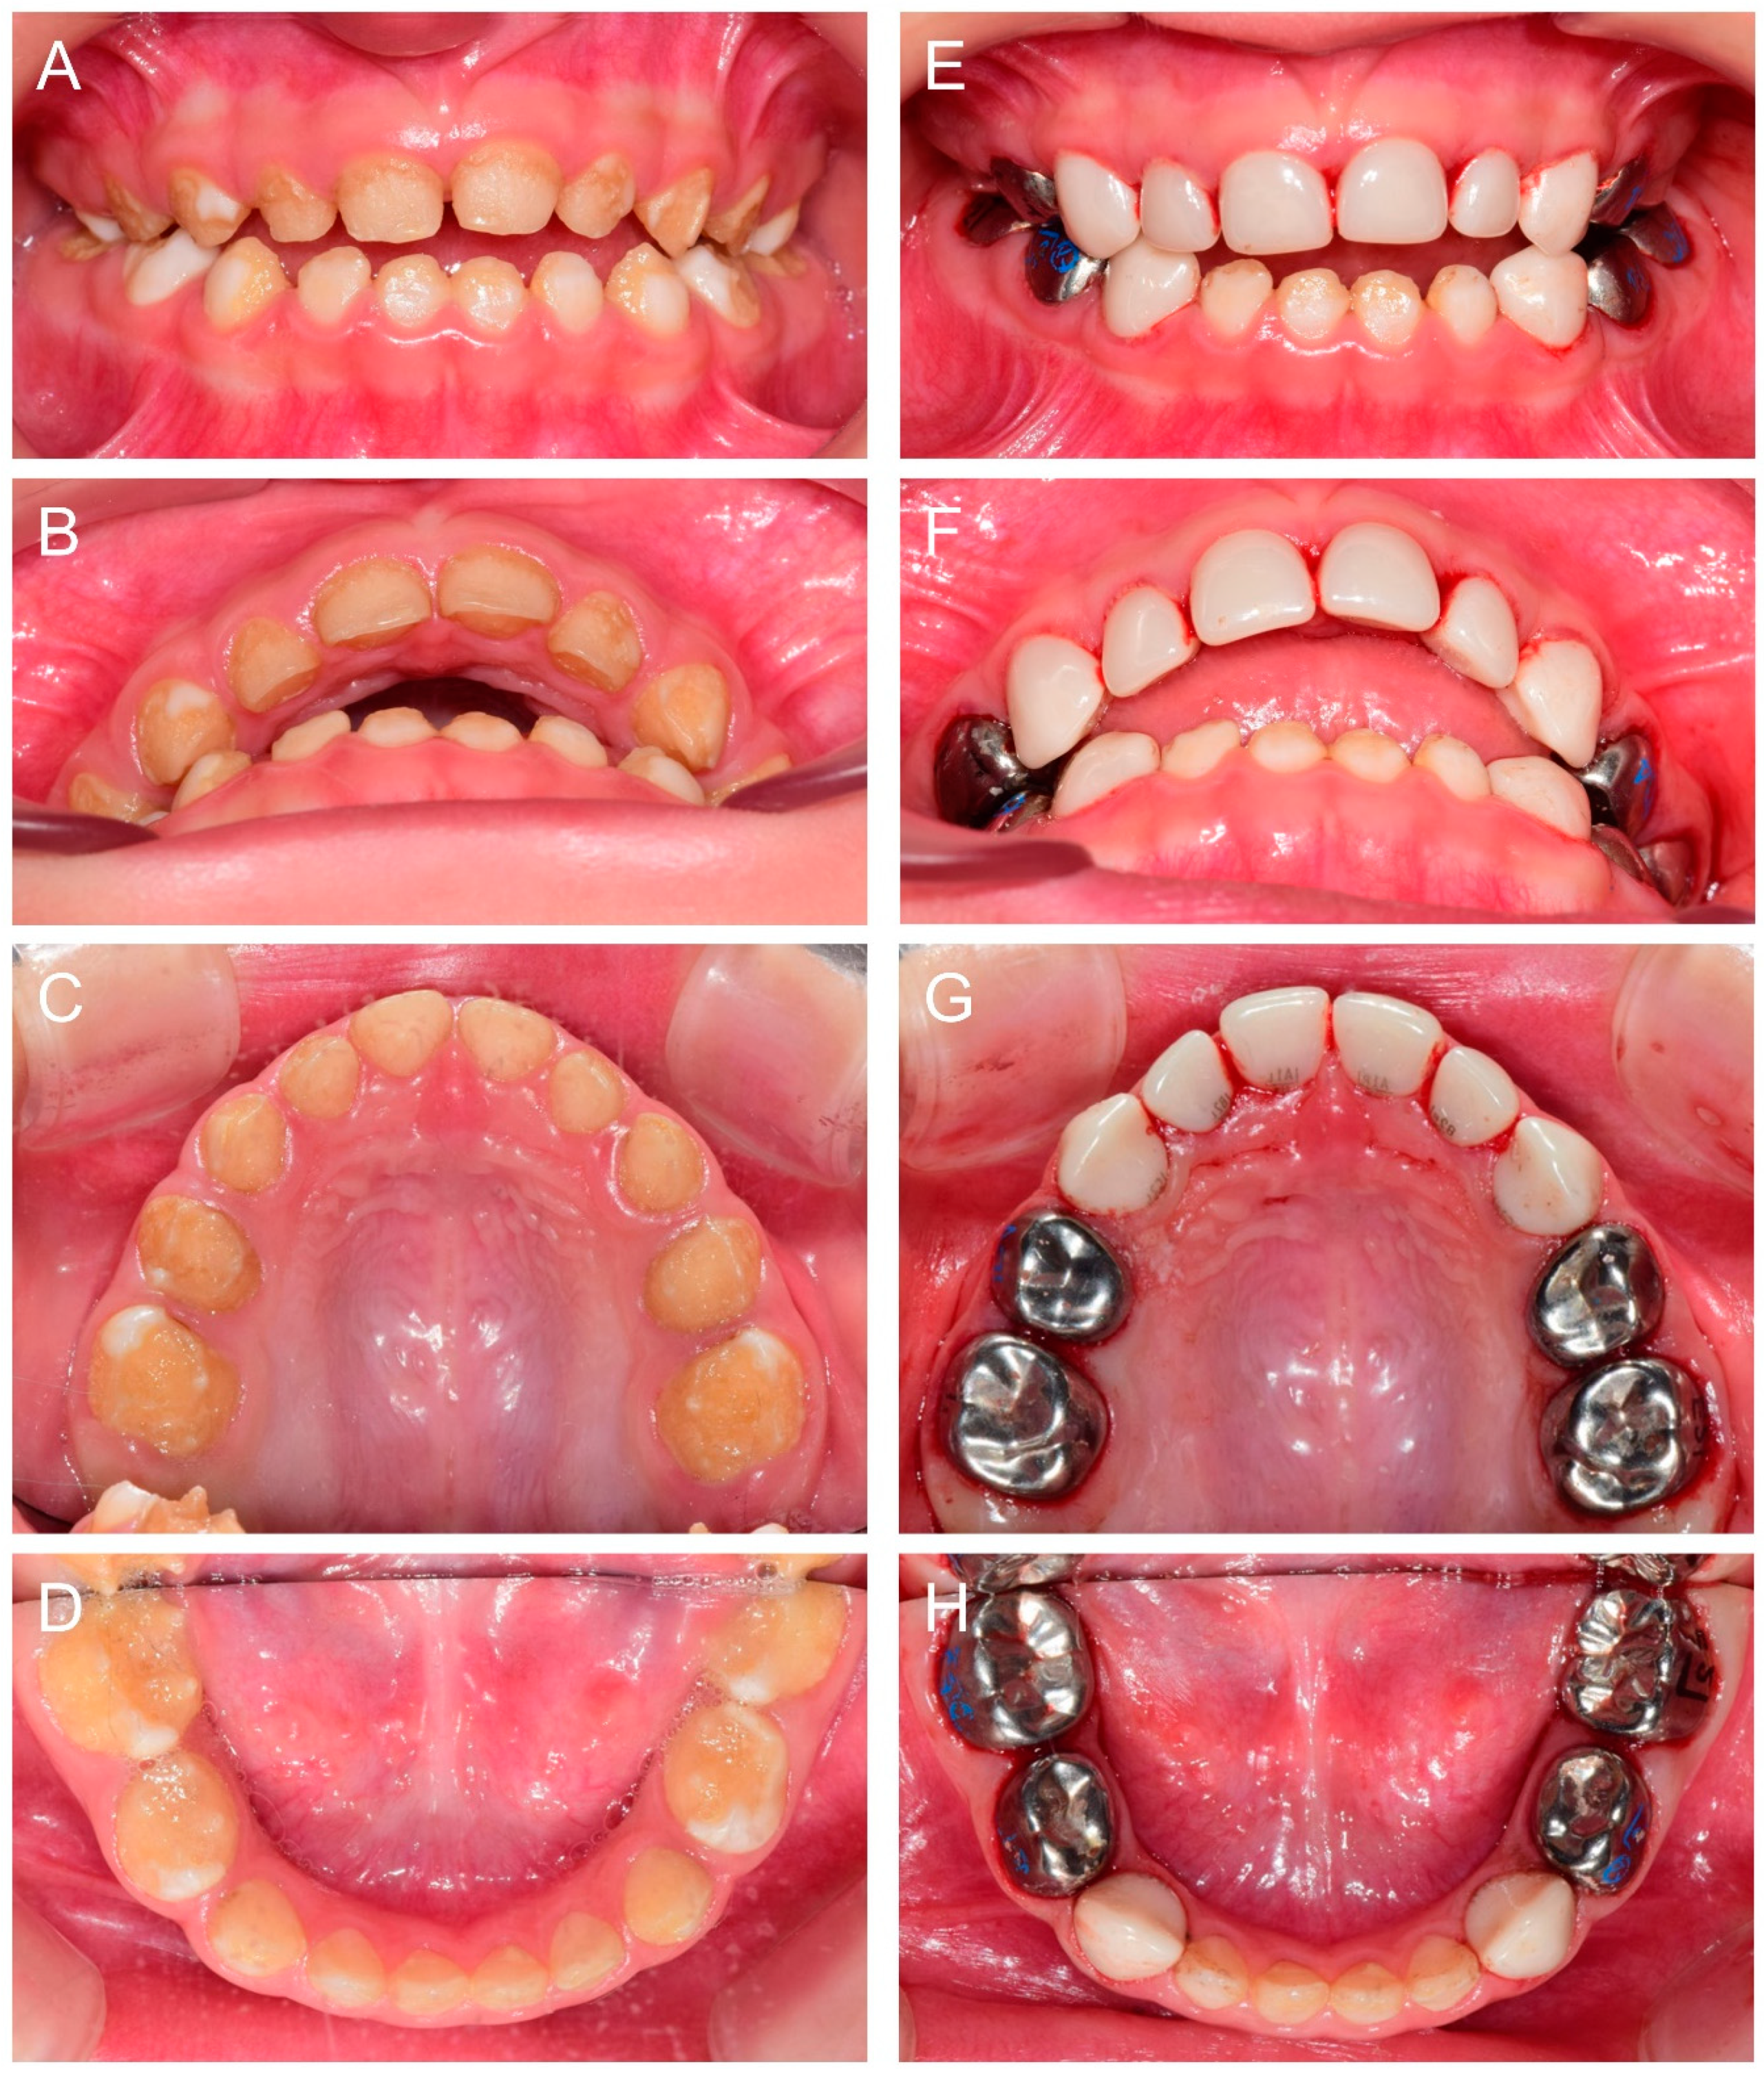

At 2Y9M, full-mouth restoration was performed under outpatient GA (Figure 2). Deciduous molars were treated with stainless steel crowns. Deciduous canines and maxillary anterior teeth were treated with zirconia crowns. Deciduous mandibular anterior teeth were left untreated. At the 3Y11M follow-up (Figure 3), good oral health was maintained, and the anterior open bite was spontaneously corrected with the discontinuance of the finger sucking habit.

Figure 2.

Clinical photos of the proband (IV:3). (A–D) Clinical photos of the proband before the treatment at age 2 years 9 months. (E–H) Clinical photos of the proband after the treatment. The deciduous molars were treated with stainless steel crowns, and the deciduous canines and maxillary anterior teeth were treated with zirconia crowns. The deciduous mandibular anterior teeth were left untreated.